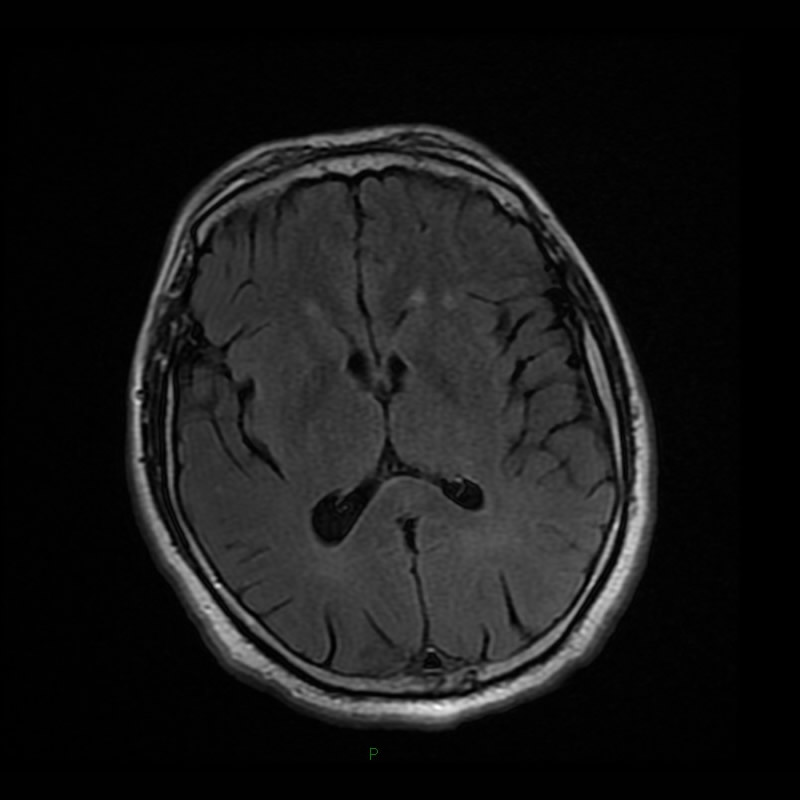

Septiembre 2021. Clínica Vélez Sársfield Paciente masculino de 47 años, cursando infección por SARS CoV-2, presenta afasia mixta y disartria